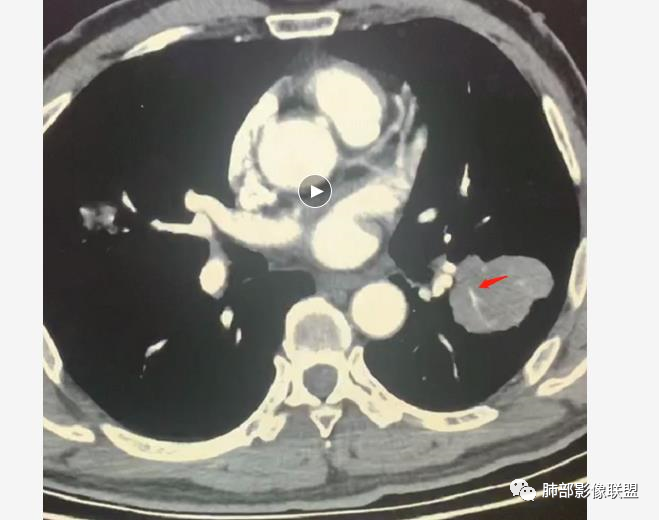

病变分布特点,胸膜下,叶间胸膜下为主,呈大小不等结节级团块影,部分病灶内见支气管影,病灶收缩不明显,从分布及慢性发病看,隐球和淋巴瘤都可,补充增强,病灶内见血管穿行,强化不明显,支持淋巴瘤

老年男性,两肺多发结节肿块,胸膜下分布为主,部分支气管进入闭塞,增强扫描有强化,血管穿行无破坏,边缘尚光滑,周围无晕,病灶整体膨隆为主,半年病程,症状逍遥,首先考虑淋巴瘤

内部支气管稍扩张,直达远端,或受压变形、移位

内部血管走形自然,稍纤细

这里似乎稍增粗

3.支气管充气征伴或不伴支气管扩张:肿瘤细胞沿肺间质及支气管黏膜下组织浸润,支气管管壁未见明显破坏,管腔内未见肿瘤细胞充填,呈现充气支气管征;充气支气管走行自然,无扭曲、僵硬,内壁管腔光滑,支气管管壁见增厚并常有管腔的扩张,含气支气管可呈串珠样不均匀扩张,扩张明显处呈空腔样或皂泡样的囊状含气影;支气管扩张目前有两种意见:一是由于肿瘤组织起源于肺间质,肿瘤沿或跨越脏器解剖结构生长,原有解剖结构残留,周围增生的纤维结缔组织牵拉导致支气管扩张;二肿瘤侵犯支气管粘膜下植物神经丛致平滑肌张力丧失;而这类支气管扩张在肿瘤治疗后有时可消失。

支气管充气征伴扩张

4.血管造影征:肿瘤组织浸润引起间质增厚、肺泡壁破坏、肺泡腔充填,而周围充盈血管走行自然,未受肿瘤侵犯。血管造影征